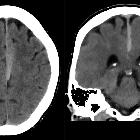

subdurales Hämatom an der Falx cerebri

Subdural

hemorrhage • Parafalcine subdural hemorrhage - Ganzer Fall bei Radiopaedia

subdural hematoma after epidural anesthesia: a case report and review of the literature. Computerized tomography of the head showing bilateral parafalcine subdural hematomas (arrow)